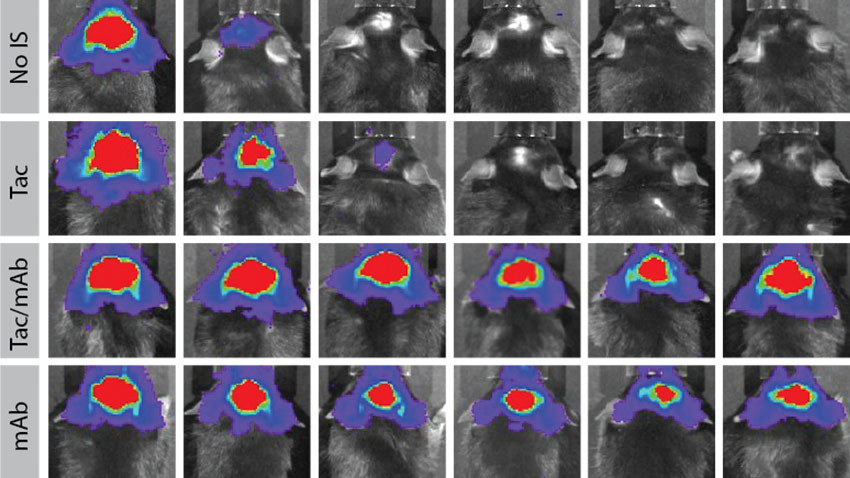

在这项研究中,研究人员使用单克隆抗体抑制小鼠的免疫系统,并将结果与传统的免疫抑制药物他克莫司和霉酚酸酯进行比较。他们使用荧光素酶(一种使萤火虫发光的蛋白质)追踪植入的人类神经干细胞的存活情况。

研究结果显示单克隆抗体的抑制使小鼠大脑中的人干细胞移植能够长期存活在使用标准免疫抑制药物的情况下,大多数动物的移植细胞存活时间不超过两周,但至少可以维持6到8个月。

传统免疫抑制药物的选择性不如单克隆抗体,在本研究中,单克隆抗体靶向两种免疫蛋白。这些抗体只在少数神经系统干细胞治疗研究中被分析过。然而,这项研究追踪了长达8个月的细胞存活时间——这是对大脑和脊髓中的干细胞发表的最长时间点之一。